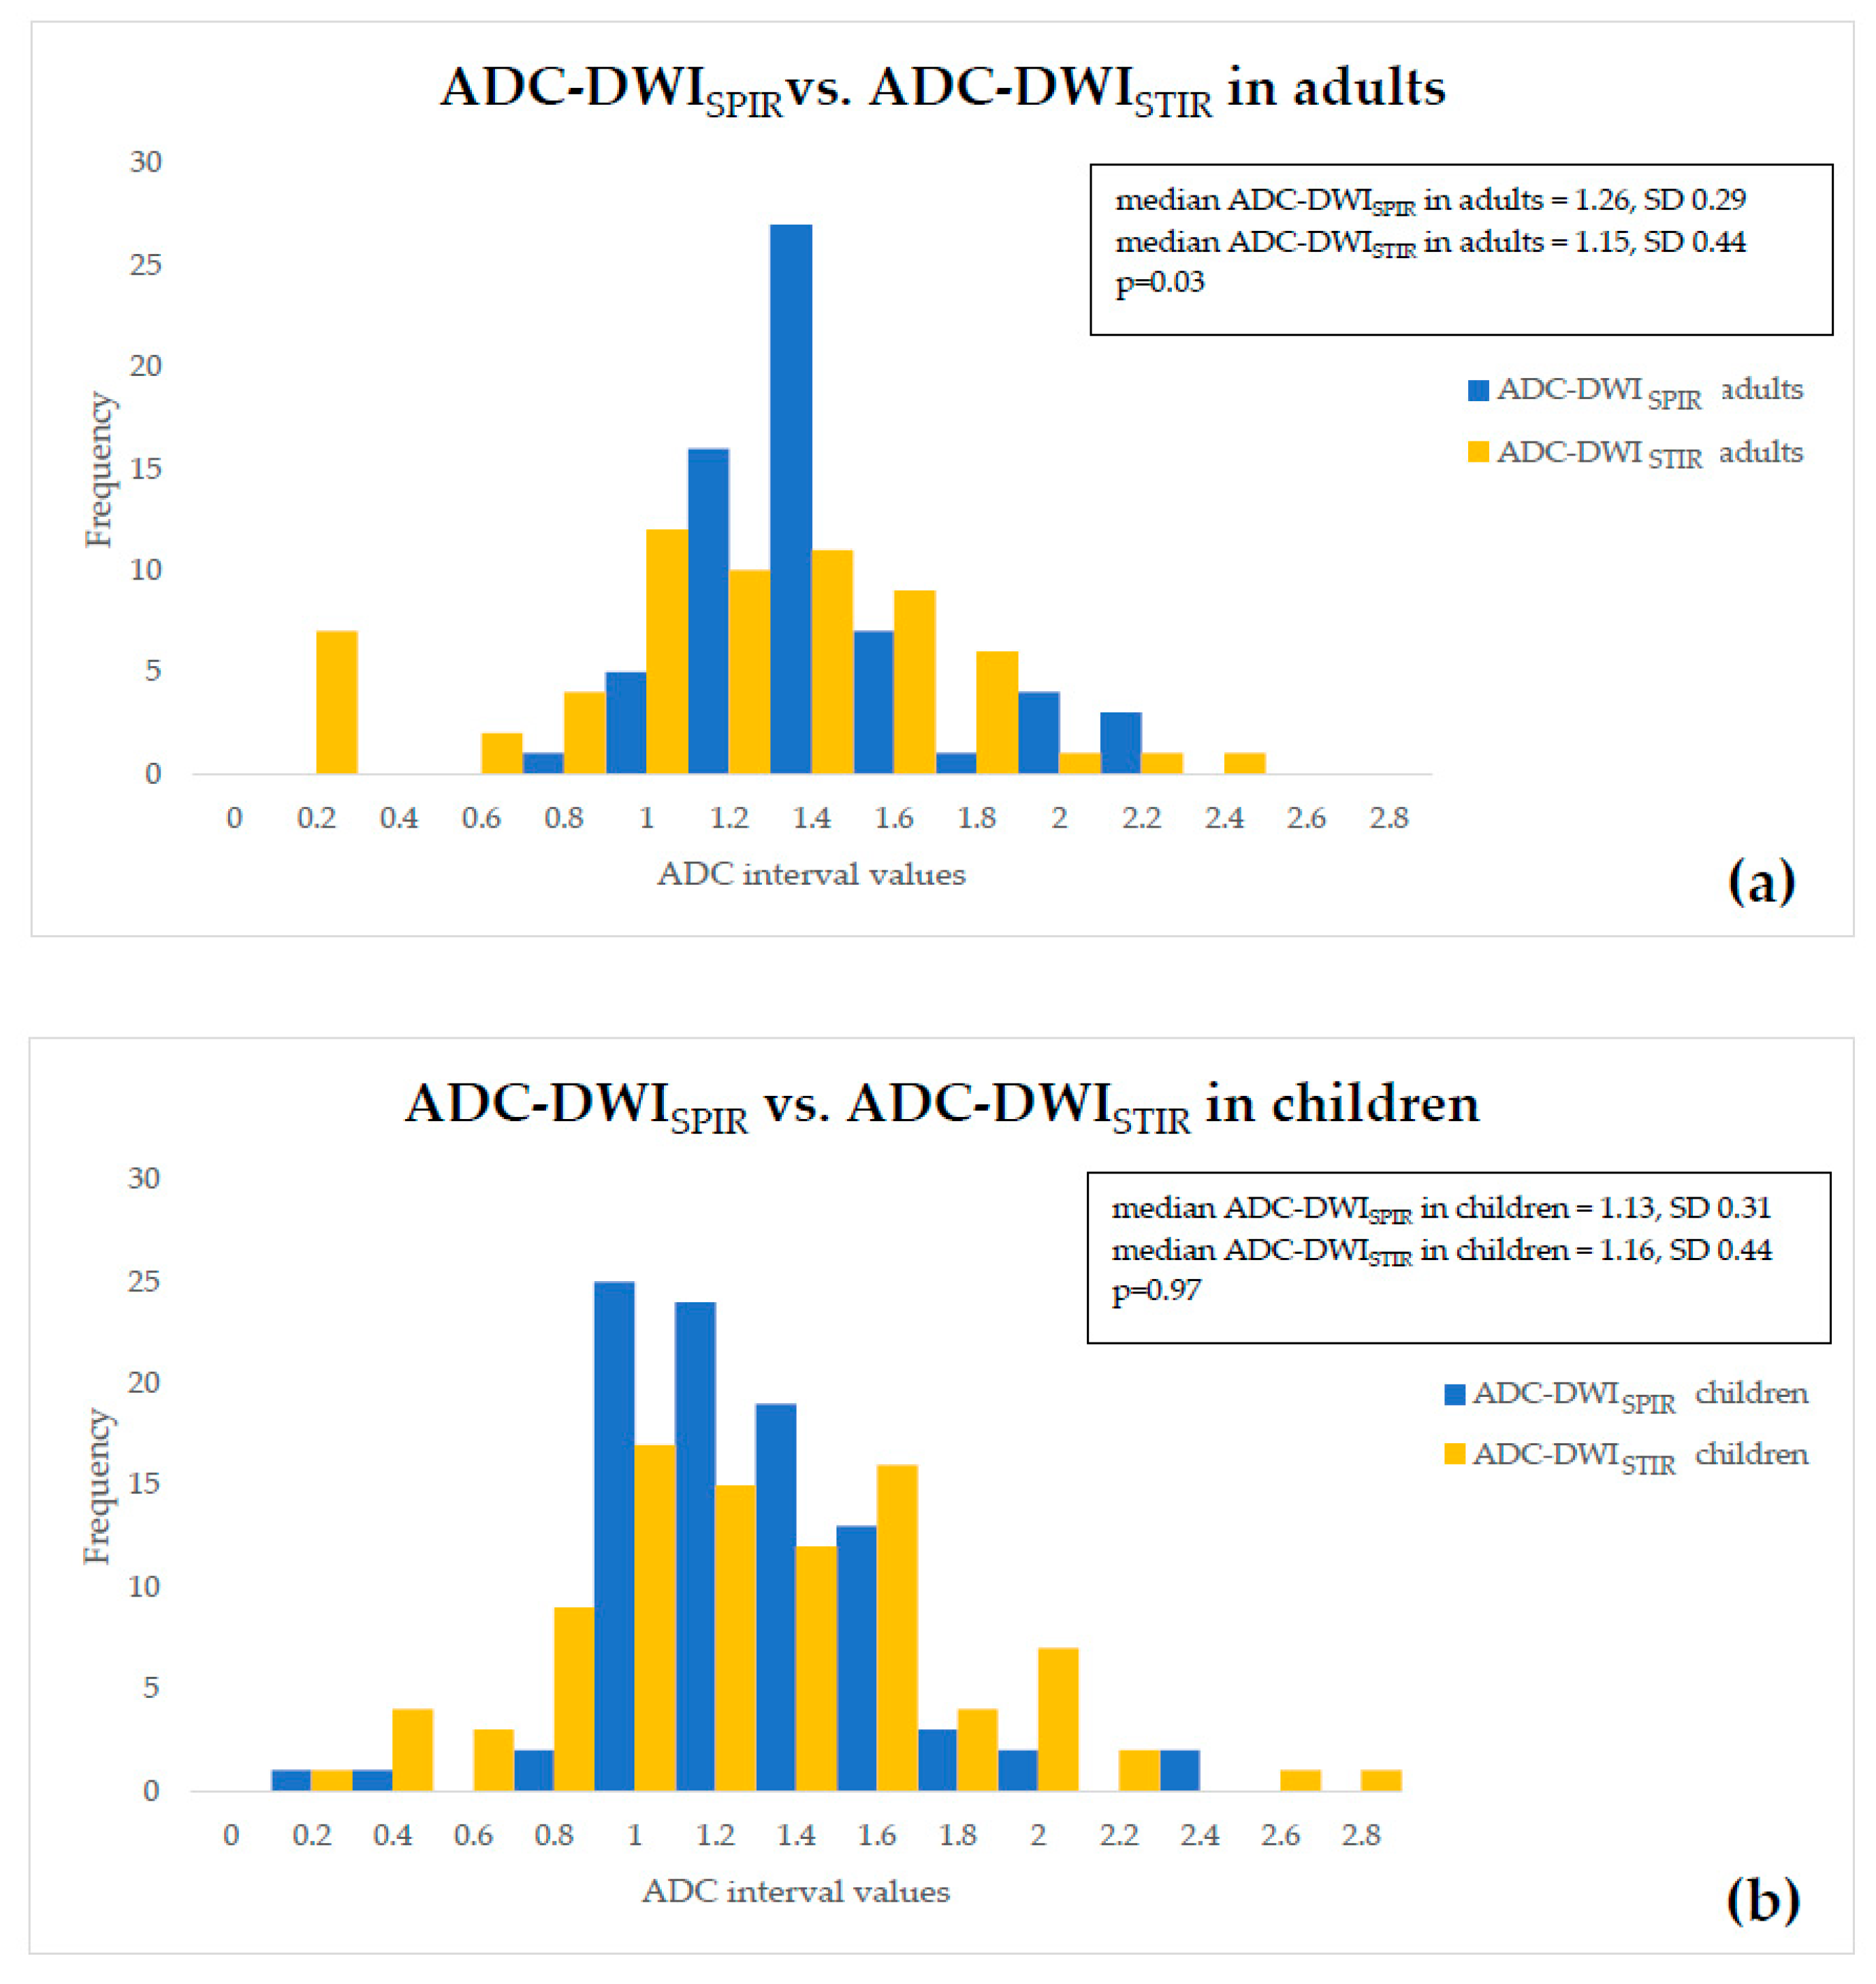

- both DWISPIR and DWISTIR techniques were compared within one patient group, both in adults and children. In this case, the analysis showed difference of 16.73% between ADC-DWISPIR and ADC-DWISTIR values in adults, being lower in DWISTIR (1.31 × 10−3 mm2/s, SD 0.29, vs. 1.09 × 10−3 mm2/s, SD 0.49; p = 0.03), but did not show difference between ADC-DWISPIR and ADC-DWISTIR values in the children’s group (1.16 mm2/s × 10−3, SD 0.31, vs. 1.20 × 10−3 mm2/s, SD 0.44, p = 0.97).